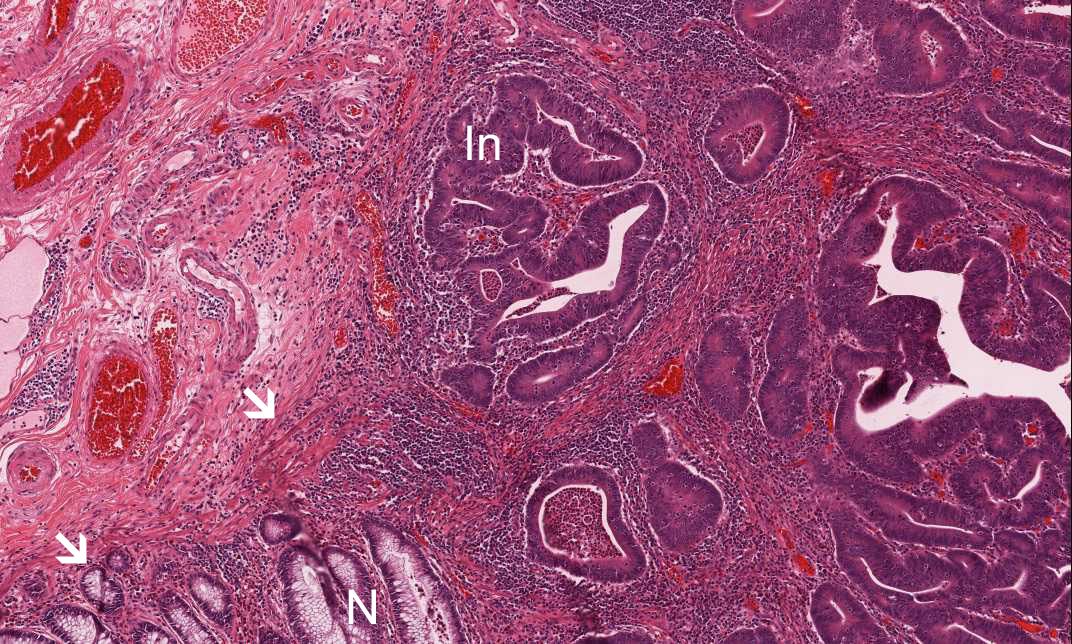

Area 3: This image is taken at the edge of the tumor where you can see the the relationship between the normal area (N), muscularis mucosa (arrow) and the invading tumor (In).

Hematoxylin & eosin

Area 3: This is another area showing the invading carcinoma. Note that necrotic debris are present in the lumens of the neoplstic glands. This is a very common feature for adenocarcinoma of the colon.